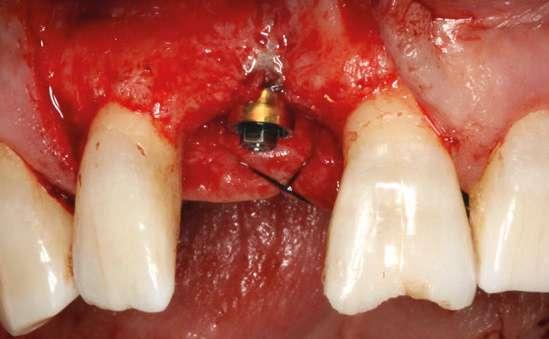

laterales se ponen de manifiesto aún más varias lesiones de esmalte que indican la parafunción en el paciente, unido a los desgastes excesivos en varias zonas (figuras 3 y 4). El paciente acude por dolor y movilidad en la pieza 11, que se ha incrementado en los últimos días, además de sensación de “diente crecido” que como podemos ver en las fotografías iniciales es real, ya que el diente se encuentra ligeramente extruido en relación con el contralateral. Estos signos parecen indicarnos una fractura o fisura. En la fotografía oclusal, podemos observar el desplazamiento del diente debido a la movilidad (figura 5). Posteriormente se realiza un sondaje positivo de la pieza, que lleva a 11 mm por lo que se confirma la sospecha de fractura y se procede a la exodoncia del diente, realizándose una regeneración posterior del alveolo con PRGF-Endoret y

esperándose 4 semanas hasta el cierre de los tejidos blandos y la neoformación ósea inicial para la colocación de un implante temprano. Cuatro semanas después, realizamos un cone-beam de control para conocer el estado del tejido óseo y poder planificar el implante. En el corte seccional observamos que se ha regenerado por completo el lecho receptor y tenemos un hueso óptimo para la inserción del implante, que por el tiempo transcurrido además es muy sencillo de expandir, con el propio implante generándose una expansión atraumática que nos permitirá ganar anchura ósea y con un implante estrecho de 3,5 mm de diámetro logramos posicionarlo sin dañar la desembocadura del nervio incisivo (figura 6). En cuanto a la longitud, con 7,5 es suficiente, no necesitándose un tamaño mayor para un correcto rendimiento biomecánico posterior.

Colocamos el implante generándose una ligera expansión vestibular, como mostramos en las imágenes intraoperatorias, para posteriormente ser sobrecorregido con hueso autólogo obtenido del fresado, embebido en PRGF-endoret y lograr una mayor anchura vestíbulo-lingual en la zona de colocación del im-

plante, clave para lograr una mejor estética y además un mantenimiento de los tejidos periimplantarios a largo plazo. En la fase quirúrgica colocamos además el transepitelial unitario para la realización de la carga inmediata y la colcación de un provisional atornillado horas después de la cirugía (figuras 7-14).

Figuras 7 y 8. Perforación inicial y colocación del implante expandiendo la zona vestibular.

Figuras 9 y 10. Visión vestibular tras la inserción del implante y colocación del transepitelial unitario para comenzar la carga inmediata.

Figuras 11 y 12. Sobre-corrección vestibular y cierre primario de los tejidos con un monofilamento no reabsorbible alrededor de la tapa de protección del transepitelial.